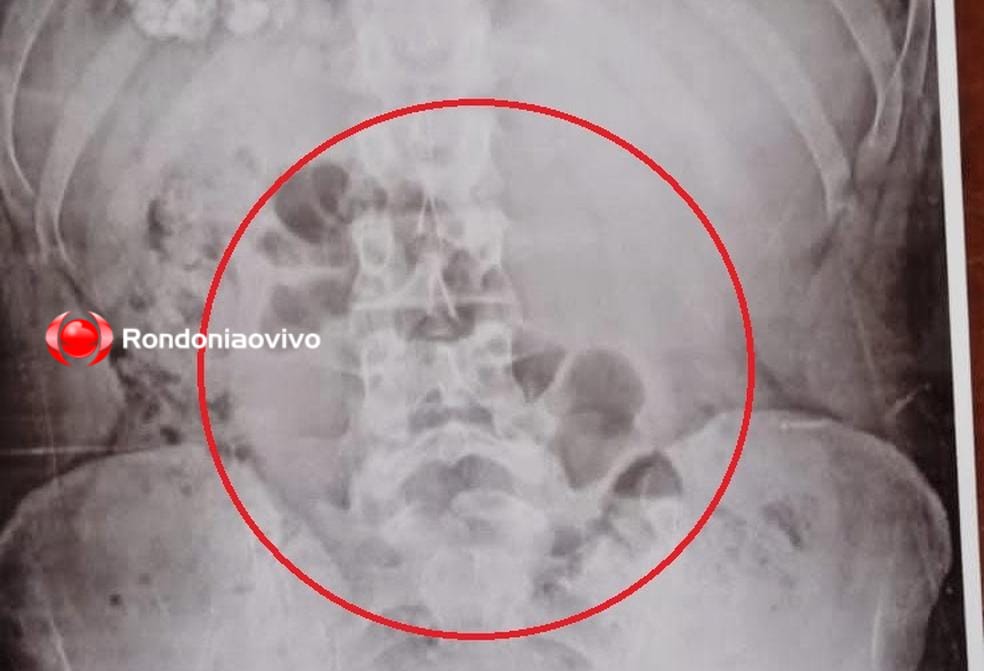

O ex-deputado estadual e ex-presidente da Assembleia Legislativa do Estado de Rondônia (ALE-RO), Carlão de Oliveira, foi internado em estado grave no Hospital Central, em Porto Velho, onde se encontra na UTI, após sofrer um infarto.

Carlão, que é pai do deputado estadual Jean de Oliveira, começou a passar a mal ainda na noite de segunda-feira (05) em sua casa quando sofreu o ataque. Logo ele foi levado para uma Unidade de Pronto Atendimento (UPA), porém devido a gravidade do infarto que sofreu logo foi transferido para a UTI do HC.